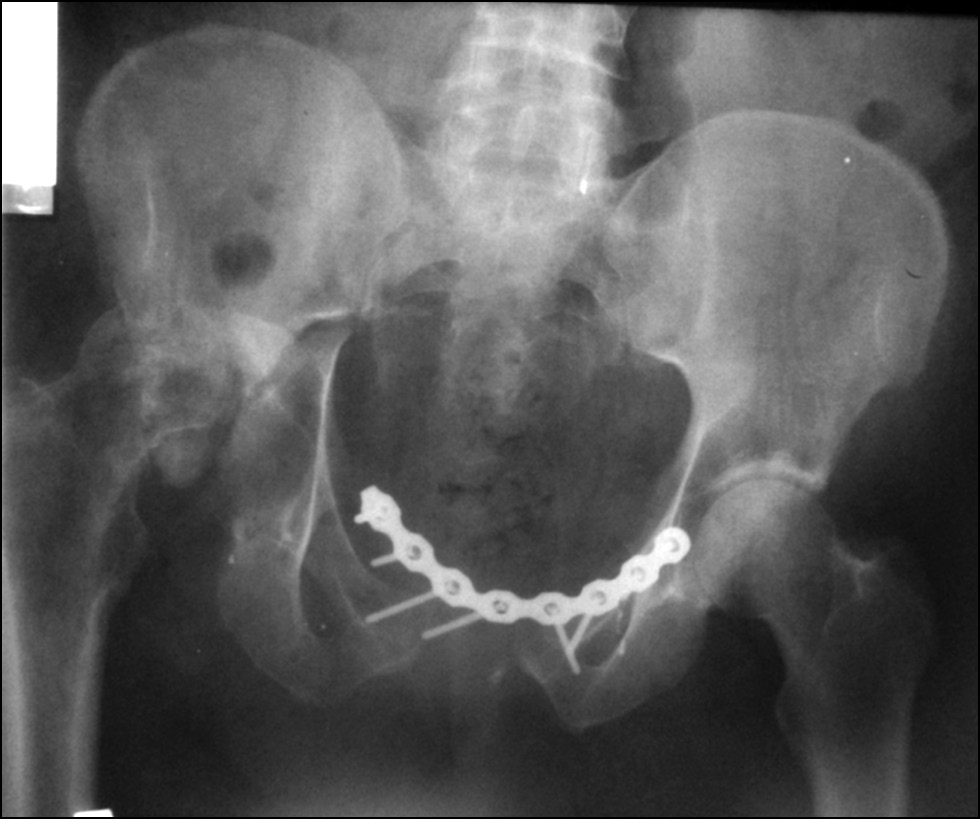

После низведения левой половины таза на втором этапе нами выполнен металлодез переднего полукольца таза двумя реконструктивными пластинами и произведена фиксация левого крестцово-подвздошного сочленения двумя канюлированными винтами (рис. 7, 8).

Рис. 7. Обзорная рентгенография таза после операции

Fig. 7. Plain radiography of the pelvis after surgery

Рис. 8. Каудальная рентгенография таза. Проекция in-let

Fig. 8. Caudal radiography of the pelvis. In-let projection

Несмотря на то, что была произведена стабилизация переднего полукольца таза двумя пластинами и фиксация заднего отдела тазового кольца, когда через 14 сут после хирургического лечения пациентка начала двигательную активность, была выявлена дестабилизация металлоконструкции (рис. 9).

Рис. 9. Обзорная рентгенография таза. Дестабилизация металлоконструкций

Fig. 9. Plain radiography of the pelvis. Destabilization of metal structures